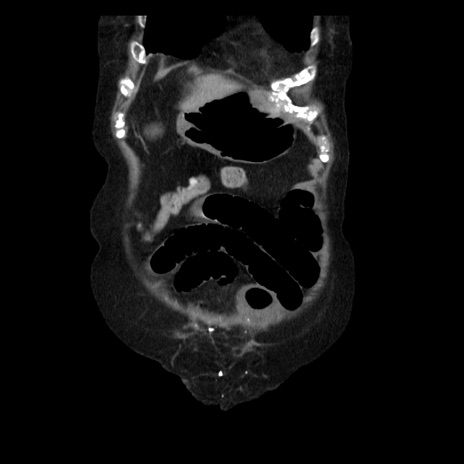

横断像

症例14(冠状断像)

【症例】 90歳代女性

【主訴】 腹痛・嘔吐

【現病歴】今朝から左側腹部痛を認めた。 経過観察していたが、嘔吐を認めたため来院。

【既往歴】 子宮癌術後

【身体所見】 意識清明、BP 127/54mmHg、P 98bpm Sp02 95%(RA)、BT 35.8°C、腹部平坦・軟腸ぜん動音聴取良好、右下腹部圧痛(+) 反跳痛なし

【データ】WBC 9800、CRP 0.46